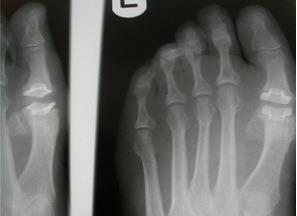

Diagnosis of hallux limitus is made by both physical examination of your foot and by x-ray examination. There is a commonly mild swelling and bony prominence associated with the first metatarso – phalangeal joint behind the big toe.

X-ray examination of the foot will reveal the true severity of the condition. It will allow the physician to evaluate the joint for bone spurs, decrease in joint space, flattening of joint surfaces, and loose bodies in the joint. X-rays can also reveal the causes of hallux limitus such as an elongated or elevated first metatarsal.

- To allow the head of the bone to be raised or lowered, there is the Reverdin-Green-Laird-Todd procedure. In this procedure a triangular-shaped wedge is removed both from the top and from the side. This procedure allows one to correct a bunion in three dimensions. An example is demonstrated with the x-ray on the right.